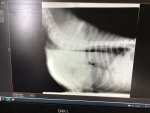

Oh Homer, you angel - I hope it brings useful information. And I hope Potters Bar has plenty to entertain you while you wait - make time for at least one treat for yourself xHomer is having a swallow study fluoroscopy done at the RVC. After being sick on their one and only carpeted area he was impeccably behaved and trotted off with the vet and the student vet happily after I told him that the vet would feed him. I have to hang around Potters Bar to pick him up later.